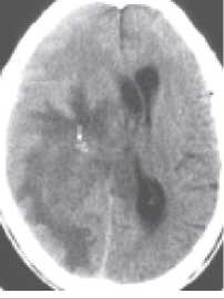

Пухлини головного мозку виявляються променевими методами дослідження за прямими та побічними ознаками. До прямих ознак належить безпосереднє виявлення пухлини у вигляді об’ємного утворення, до побічних - перифокальний набряк, мас-ефект (зміщення сусідніх структур мозку та деформація шлуночків), звапнення в пухлині, деструктивні зміни у кістках черепа та деякі інші (мал. 292, 294). За допомогою КТ та МРТ пухлина виявляється у вигляді ділянки зміненої денситометричної щільності (гіпер- або гіподенсивної), або сили МР-сигналу (гіпер- або гіпоінтенсивного) (мал. 293). Форма ділянки частіше неправильна, структура - неоднорідна. Ізоденсні та ізоінтенсивні пухлини головного мозку виявляються за непрямими ознаками, а також за допомогою внутрішньовенного контрастування рентгеноконтрастною речовиною (КТ) чи гадолінієм (МРТ), при якому денситометрична щільність або інтенсивність сигналу пухлини підвищується більшою мірою, ніж здорової мозкової Тканини.

Мал. 292. Комп’ютерна томограма пухлин головного мозку (схема):

А - внутрішньомозкова пухлина,

Б - внутрішньошлуночкова пухлина, В - невринома ділянки внутрішнього слухового отвору.

1 - гіподенсивна зона набряку навколо пухлини; 2 - фіксація контрасту в пухлині; 3 - ампутація порожнини шлуночка; 4 - відтиснення четвертого шлуночка; 5 - невринома слухового (присінково-завиткового) нерва.